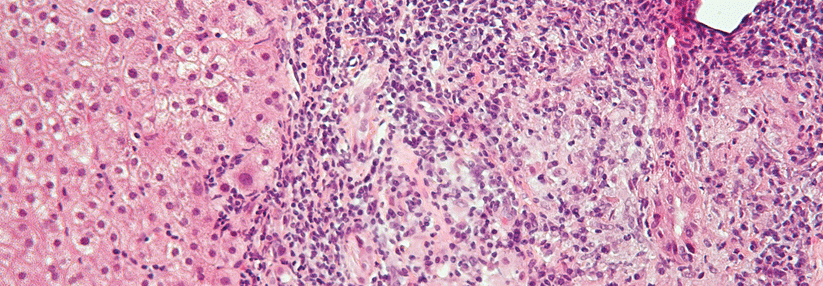

Die primär biliäre Cholangitis (PBC) ist mit einem Anteil von 80–90 % vor allem eine Erkrankung von Frauen, erklärte Prof. Dr. Christoph Schram von der Medizinischen Klinik I an der Universitätsklinik HH-Eppendorf. Die Prävalenz liegt bei 40/100.000 und das mittlere Erkrankungsalter bei 50 bis 60 Jahren. Die Diagnose kann gestellt werden, wenn zwei der folgenden drei Kriterien erfüllt sind:

• chronische Cholestase

• antimitochondriale Antikörper (AMA, bei über 90 % positiv) oder typische antinukleäre Antikörper (ANA, etwa 70 % der AMA-negativen Patienten)

• typische Histologie